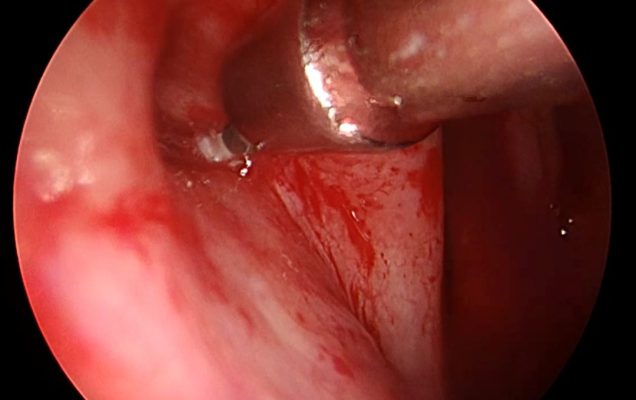

Balonikowanie trąbek słuchowych (trąbek Eustachiusza) to innowacyjna, małoinwazyjna metoda terapeutyczna stosowana u pacjentów z ich przewlekłą dysfunkcją. Schorzenie to może objawiać się uczuciem pełności w uszach, autofonią, pogorszeniem słuchu, nawracającymi infekcjami oraz trudnościami w wyrównywaniu ciśnienia – szczególnie odczuwalnymi podczas lotów samolotem czy nurkowania. Zabieg polega na wprowadzeniu przez jamę nosową cienkiego cewnika zakończonego balonikiem do ujścia gardłowego trąbki słuchowej, pod kontrolą endoskopową. Następnie balonik jest stopniowo wypełniany solą fizjologiczną, co pod działaniem ciśnienia około 10-12 atmosfer powoduje poszerzenie i przywrócenie drożności. Po krótkim czasie balon zostaje opróżniony i usunięty. Cała procedura wykonywana jest w znieczuleniu ogólnym i nie wymaga wykonywania widocznych nacięć.

Procedurę wykonała dr n. med. Marta Kwiatkowska, specjalizująca się m. in. w endoskopowej chirurgii ucha środkowego i zatok przynosowych.